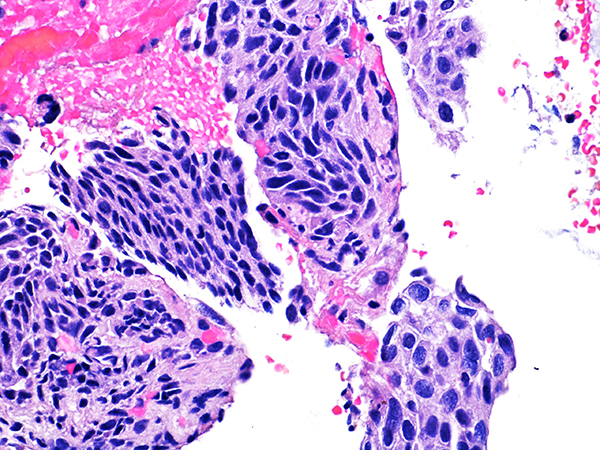

![]() Case 1

Area 2 - Soft Bx CIN 2 40x - High Power |